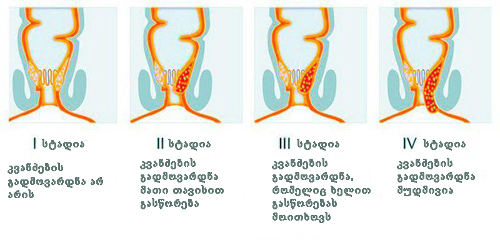

ბუასილის სტადიები

მე ქსელში ვნახე ფოტო, რომელიც გავდა იმას რაც მე მქონდა. მარცხნივ ბუასილის მესამე სტადიაა (რომელიც მე მქონდა), მარკვნივ ჯანმრთელი სფინქტერი.